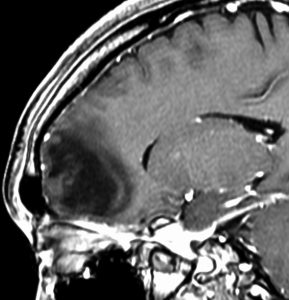

expanding, solid 固形腫瘍的なもの

壊死ではない「のう胞」を伴い,ガドリニウムで強く増強されます。グレード 4 (膠芽腫)と間違えるようなものです。しかし,のう胞はありますが中心壊死がありません。

腫瘍を大部分摘出できるので,積極的な摘出術をして,手術後には放射線化学療法を加えます。この例では,手術後の放射線治療計画の領域が狭ければ,60グレイを使用できる部位です。